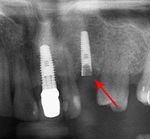

قبل زراعة الأسنان، يطلب من المريض اجراء فحص تصوير للأسنان، وعادة يطلب اجراء صورة خاصة (صورة أشعة بانوراما للأسنان) أو حتى فحص التصوير المقطعي المحوسب (CT)، للكشف والتشخيص عن حالات الأسنان التي ليس بالامكان رؤيتها من خلال الفحص الاعتيادي.

اذا كان العظم على استعداد لتلقي الزرع (أحيانا بعد سلسلة علاجات مسبقة)، يمكن البدء بعملية زرع الاسنان. يتم تثبيت المسامير المعدنية اللولبيه براغي، بعظم الفك. في سلسلة اخرى من العلاجات بعد فترة من ادخال البراغي، تبدا عمليات اعادة البناء عن طريق أخذ القياسات وانشاء التاج/الجسر. عندما يدور الحديث عن فترة الانتظار بين تركيب الغرسات وبين تنفيذ الاستبناء النهائي، فان هنالك اكثر من نهج واحد. النهج المتبع غالبا هو الانتظار لمدة 6 أسابيع على الأقل حتى تلتئم الانسجة، وأحيانا تصل فترة الانتظار لعدة شهور.